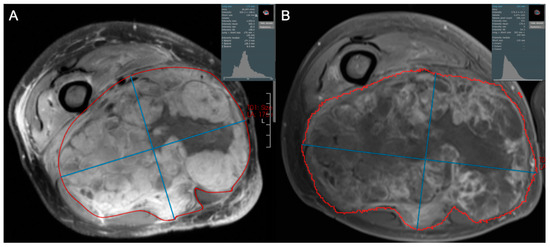

- Subhawong, T.K.; Feister, K.; Sweet, K.; Alperin, N.; Kwon, D.; Rosenberg, A.; Trent, J.; Wilky, B.A. MRI Volumetrics and Image Texture Analysis in Assessing Systemic Treatment Response in Extra-Abdominal Desmoid Fibromatosis. Radiol. Imaging Cancer 2021, 3, e210016. [Google Scholar] [CrossRef]

- Singer, A.D.; Pattany, P.M.; Fayad, L.M.; Tresley, J.; Subhawong, T.K. Volumetric segmentation of ADC maps and utility of standard deviation as measure of tumor heterogeneity in soft tissue tumors. Clin. Imaging 2016, 40, 386–391. [Google Scholar] [CrossRef]